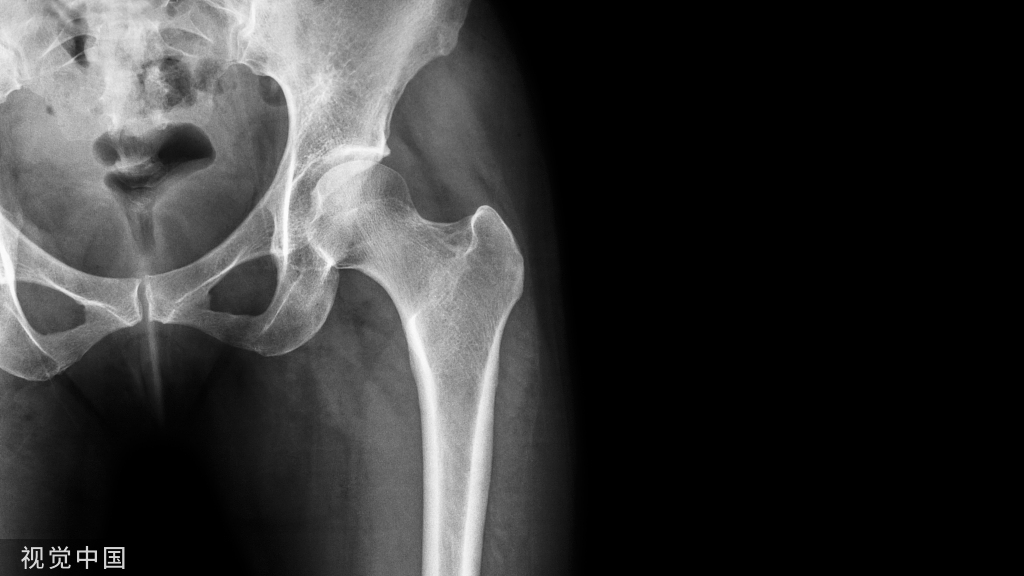

说起骨质疏松,相信大家都不陌生,但对于它的危害很多人都不了解,骨质疏松导致的骨折危害巨大,是老年患者致残和致死的主要原因之一。那么,什么是骨质疏松症?骨质疏松症是一种以骨量低下、骨的微结构破坏、骨小梁变细、断裂、导致骨的脆性增加、骨折风险增加的全身性骨病。简单来说,就是骨流失,导致骨骼疏松多孔、脆弱不堪。骨骼的脆性增加和易发生骨折是骨质疏松症的特点,所以,骨质疏松性骨折又被称为脆性骨折。